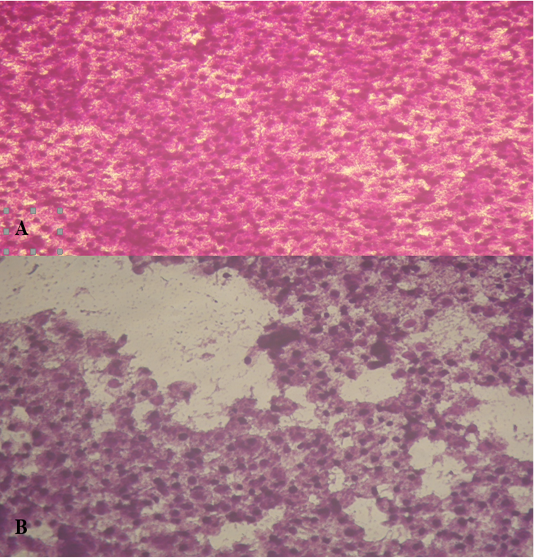

Figure 3

HepG cells treated with A. fumigatus extract at 10µg (A); at 100µ g (B).